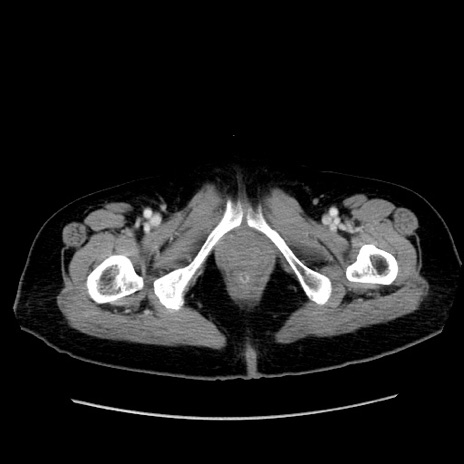

冠状断像

【症例】80歳代女性

【主訴】下腹部痛

【現病歴】約8時間前より下腹部痛の出現あり、救急外来受診。

【既往歴】両側付属器切除

【身体所見】意識清明、下腹部正中に手術痕あり、その部位に一致して圧痛と反跳痛あり。腸蠕動音は亢進。

【データ】WBC 9300、CRP 0.15